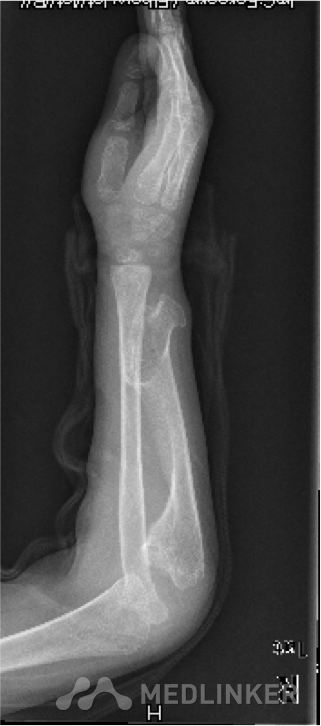

先天性骨软骨瘤病伴桡骨头脱位

桡骨头脱位

大家讨论一下这个小孩的矫形方法!